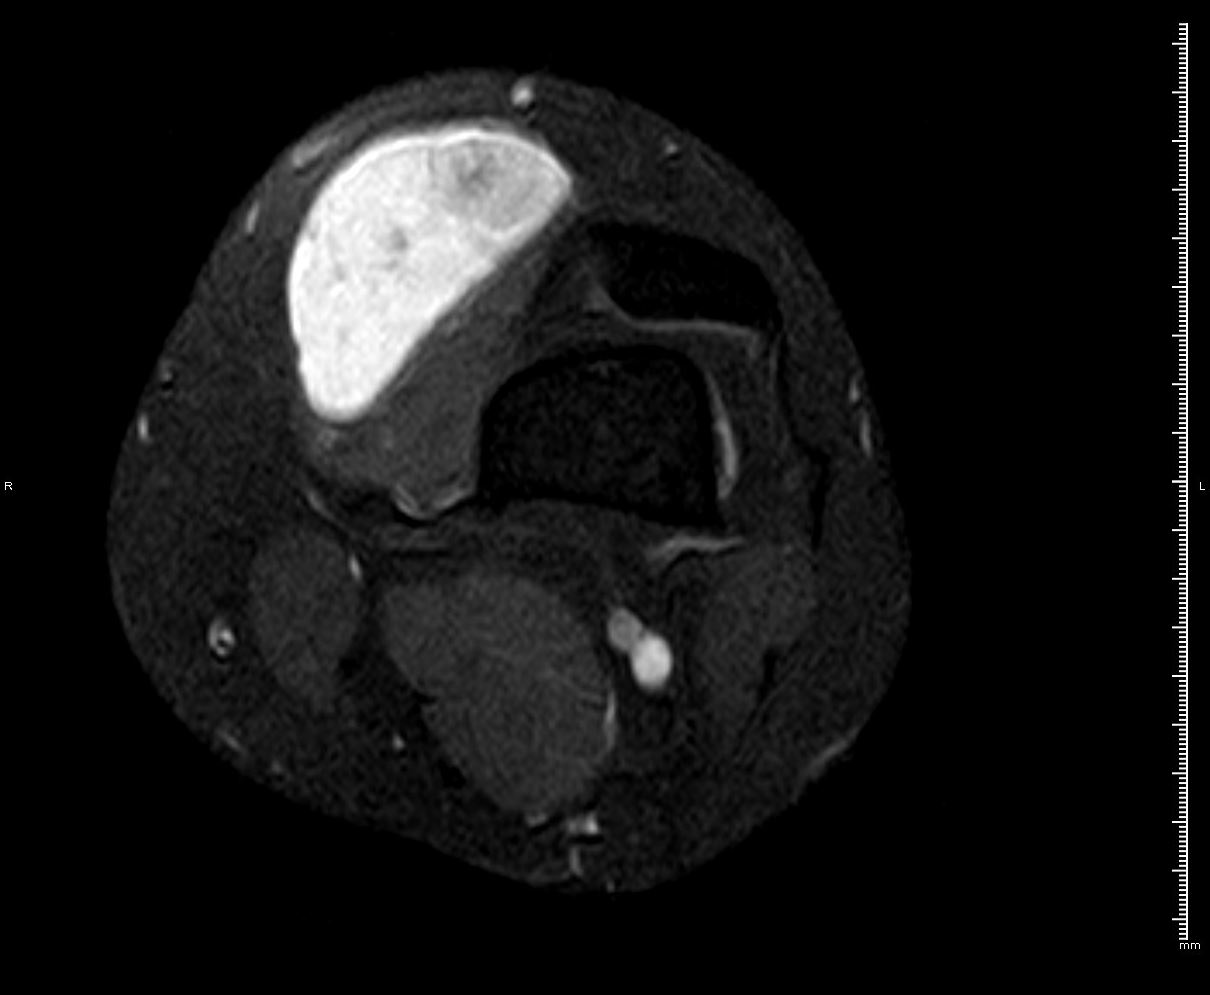

RM T1 con supresión grasa y contraste IV

HALLAZGOS RADIOLÓGICOS